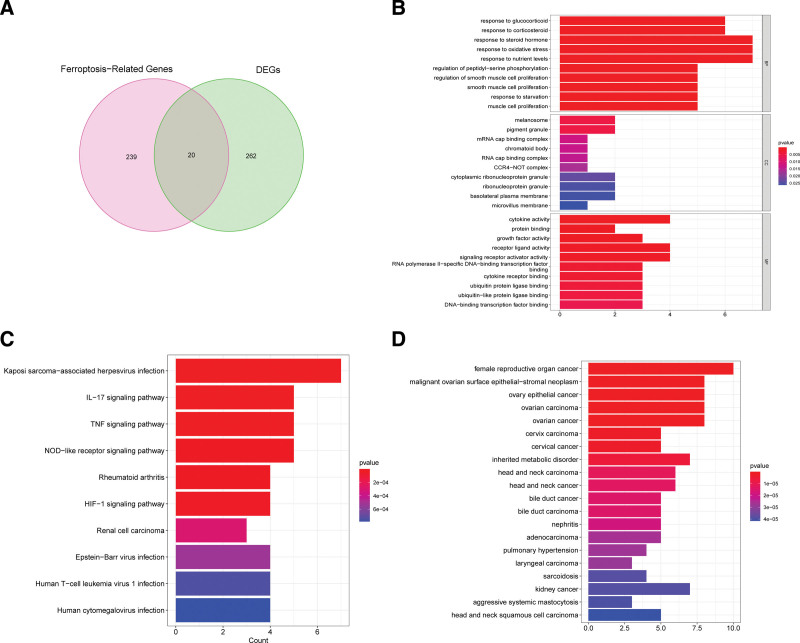

3.2. Functional enrichment analysis

We ultimately identified 20 ferroptosis-related hub genes by intersecting the obtained DEGs and 259 FRGs using the Venn diagram method (Fig. 3A). The top-ten enriched GO terms in biological processes (BP), cellular components (CC) and molecular functions (MF) were represented in Figure 3B. At the level of BP aspect, these DEGs were enriched in oxidative stress, steroid hormone, and muscle cell proliferation; for CC, these DEGs were significantly enriched in microvillus membrane, basolateral plasma membrane, and melanosome; and for MF, these DEGs were enriched in cytokine activity, protein binding, growth factor activity, and receptor ligand activity. KEGG pathway analysis was also performed and results shown that these DEGs were abundantly enriched in immune-related pathways, such as IL-7 signaling pathway, TNF signaling pathway, HIF-1 signaling pathway, Human T-cell leukemia virus 1 infection, and NOD-like receptor signaling pathway (Fig. 3C). Results of disease ontology (DO) analysis showed significant enrichment of DEGs in various cancers including ovarian cancer, cervical cancer, kidney cancer, and adenocarcinoma (Fig. 3D).

FerrDb is a database that is collected and managed manually containing integrated information ferroptosis-related genes. This study obtained 259 FRGs from the FerrDb database, including 186 ferroptosis driver genes, 132 suppressor genes and 113 ferroptosis marker genes. In this study, we screened 282 DEGs among which 126 were upregulated and 156 were downregulated. Results of followed GO enrichment analysis shown that all DEGs mainly associated with oxidative stress, steroid hormone, and muscle cell proliferation, while results of KEGG enrichment analysis indicated that DEGs were closely related to IL-7 signaling pathway, TNF signaling pathway, HIF-1 signaling pathway, Human T-cell leukemia virus 1 infection, and NOD-like receptor signaling pathway. These findings suggested that DEGs play roles in inflammatory process in OA, suggesting possible impact of these genes’ occurrence and development of OA. We subsequentially performed Venn plot to selected the ferroptosis-related hub genes in OA with the intersection of FRGs and DEGs.